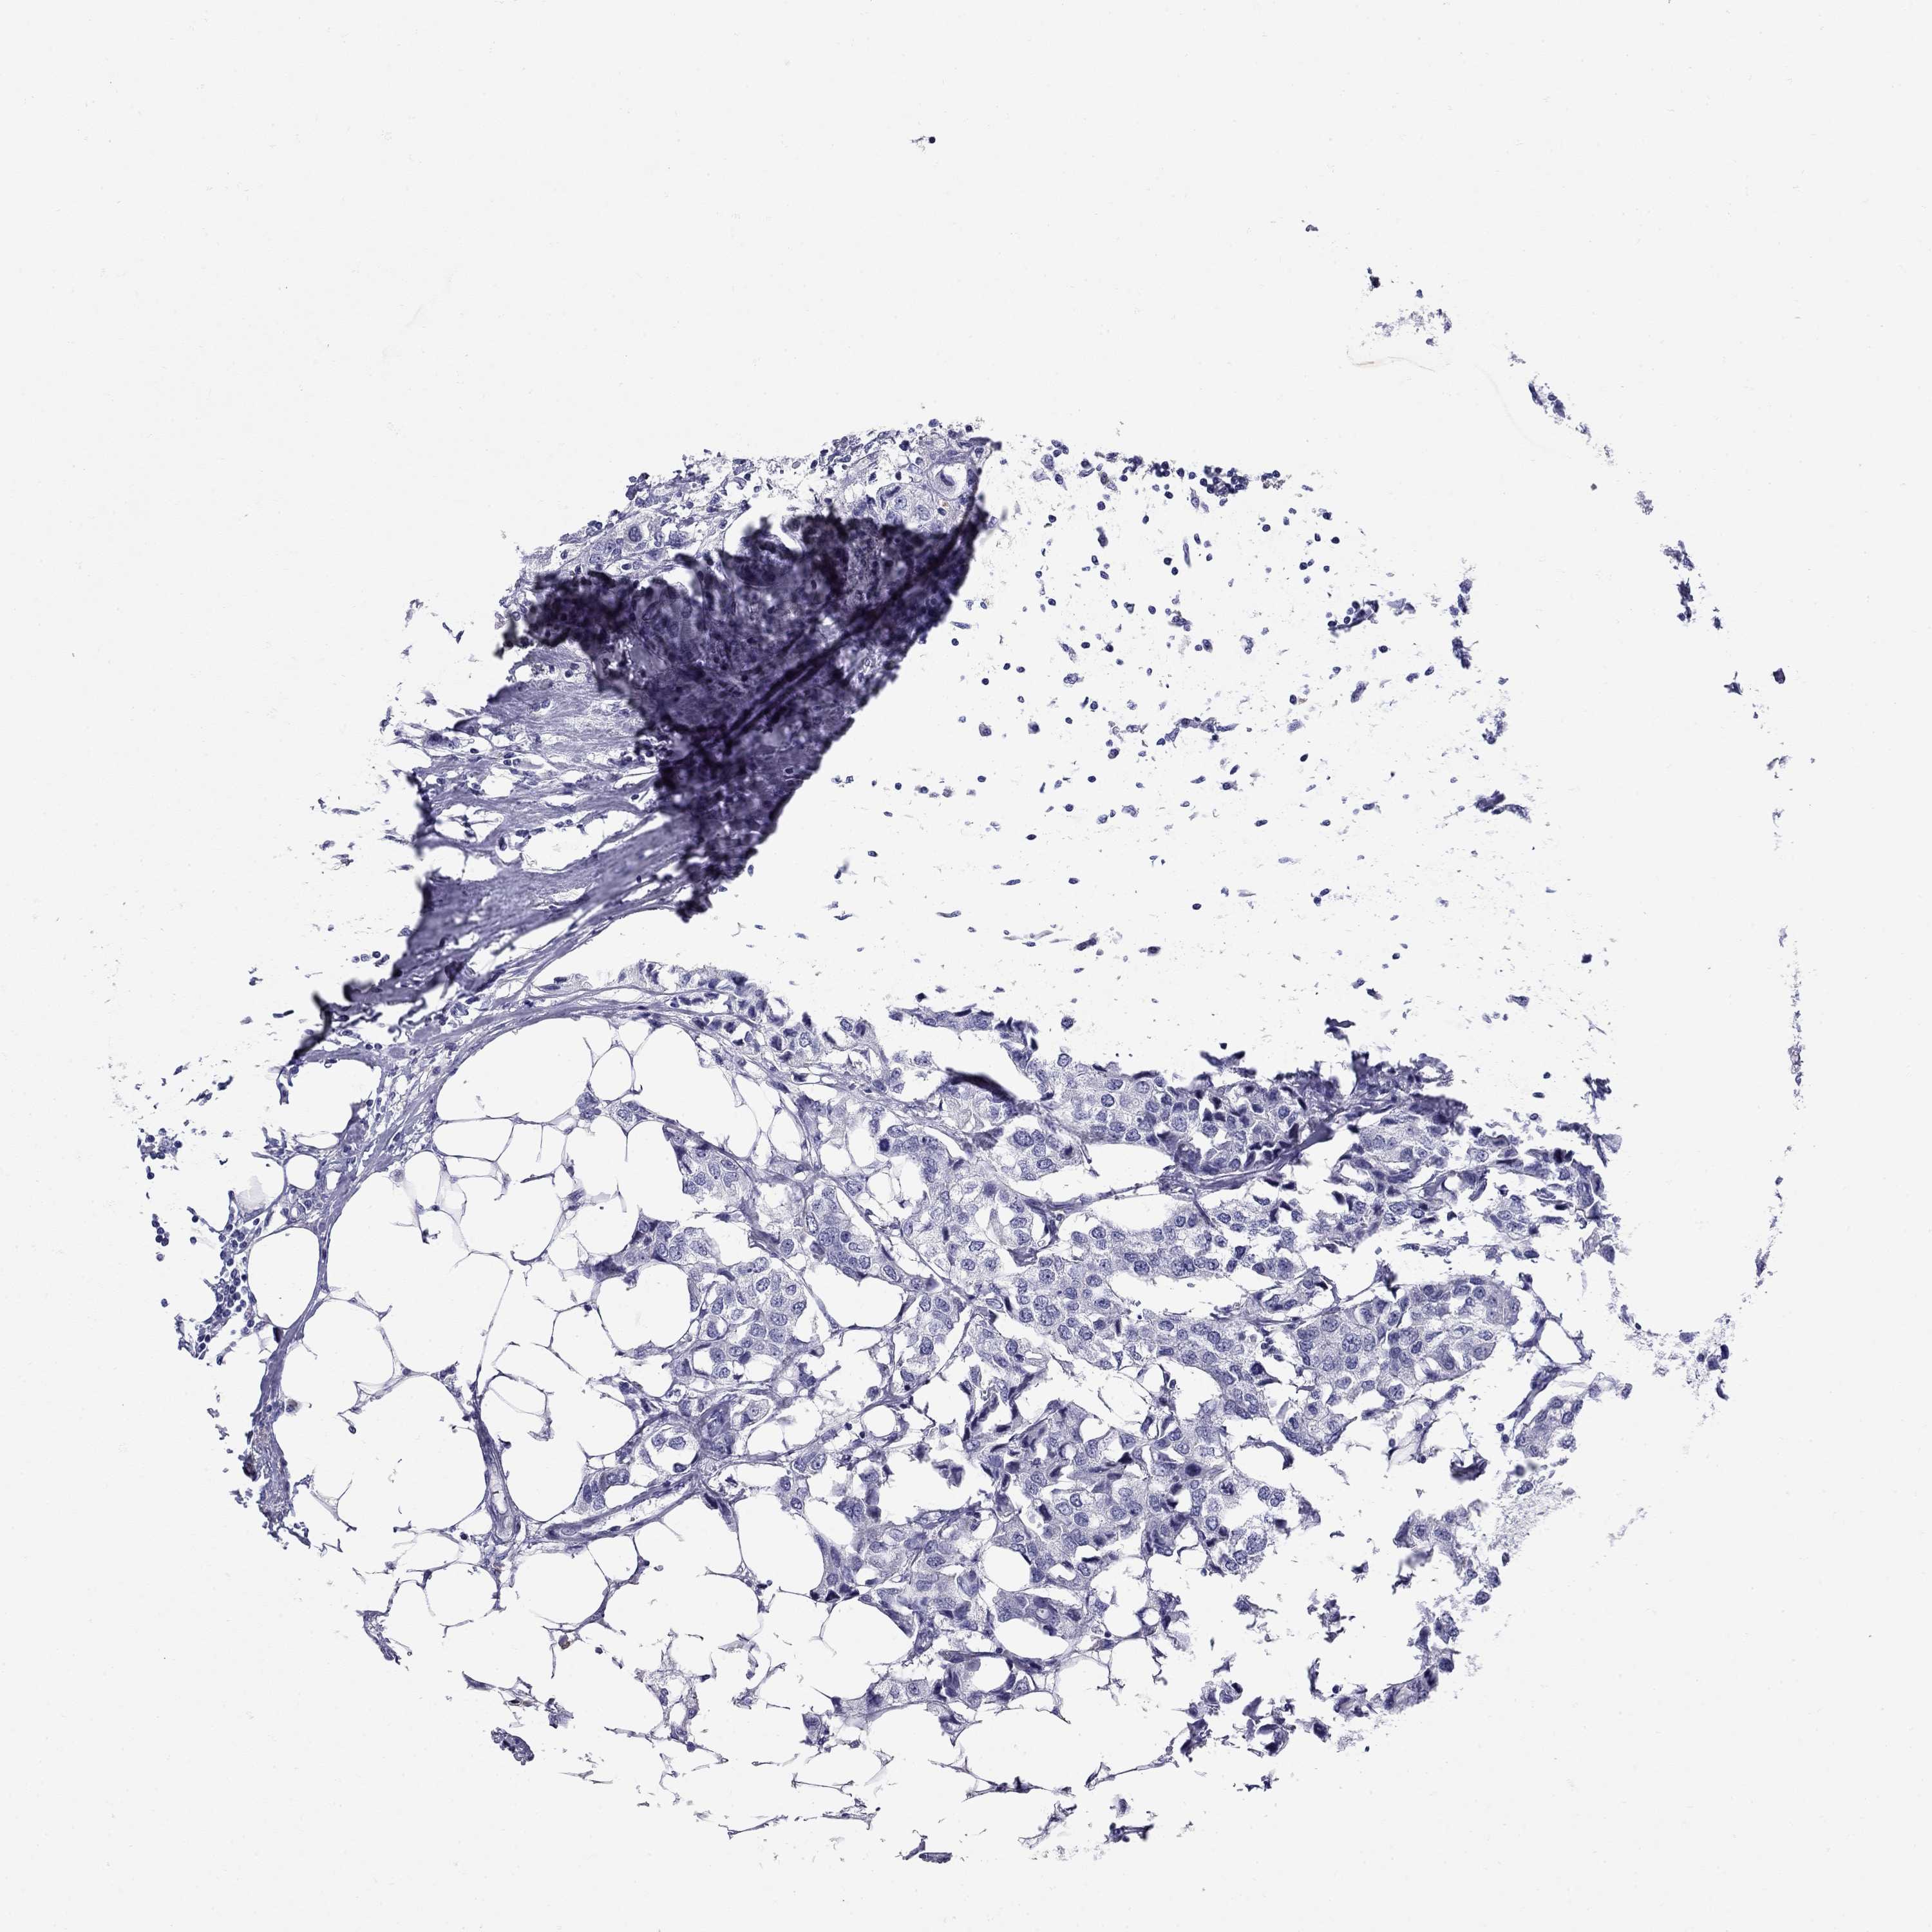

BRCA TCGA BRCA VALIDATION PROTEIN EXPRESSION

Breast cancer

Human cancer